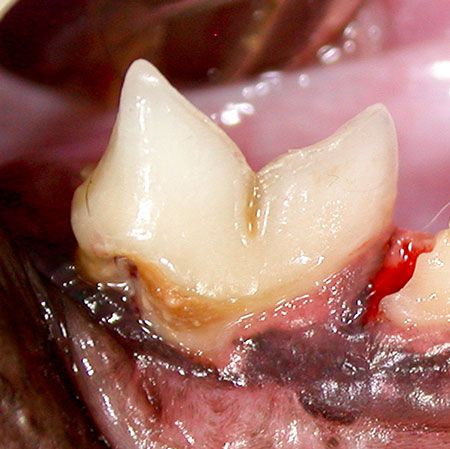

- Swollen or reddened gums

- yellow or brown teeth and loose or missing teeth

- Gingivitis. Symptoms of gingivitis include redness and swelling of the gums.

- Receding gums. A separation of the gums away from the teeth is a sign of gum disease. ...

- Bleeding. ...

- Loose teeth. ...

Periodontal disease begins when the bacteria in a dog’s mouth form a substance called plaque, which sticks to the surface of the teeth. The minerals in the saliva harden the plaque into dental calculus (tartar), which is firmly attached to the teeth. It’s not until a dog is around two to three years old that tartar begins to appear.

Periodontal disease (Periodontitis) is the most common dental issue in dogs. It is caused by the accumulation of dental plaque and tartar on the teeth, which triggers inflammation. Periodontal disease affects canine teeth and the surrounding structures (the gums and bone). Periodontitis can result in gum infections, bone loss and, ...